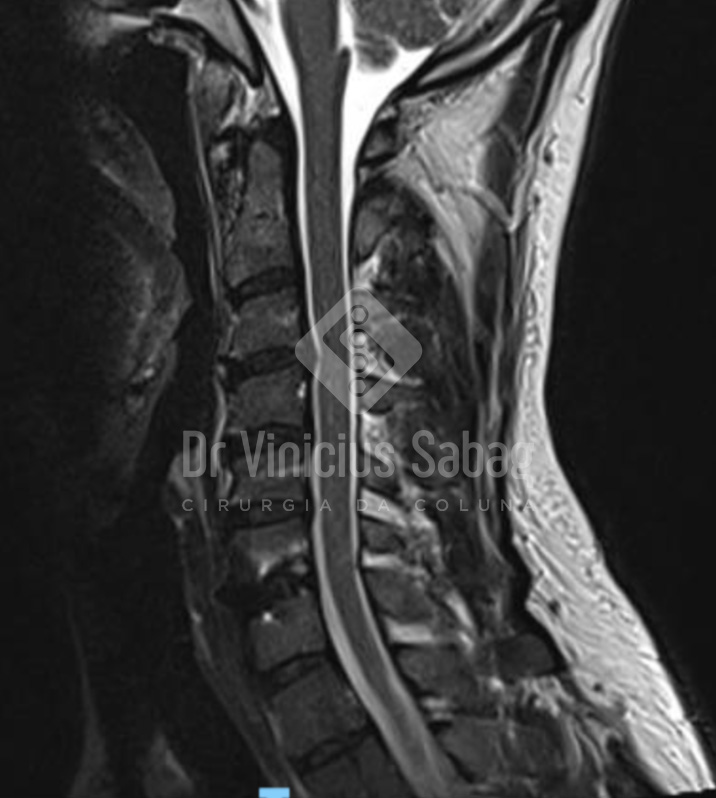

Exame pós-operatório demonstrando remoção completa da hérnia discal e adequada descompressão neural.